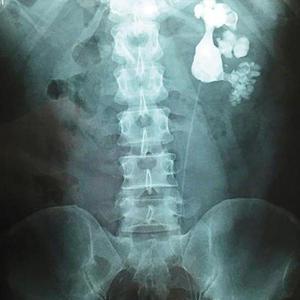

最近,新桥医院泌尿科冯医生一个月就做了20多台结石手术。前段时间,他在一位五旬男子的身体里取出了143颗结石,手术难度非常大,好在手术很成功。陈先生今年56岁,经常腹部胀痛,20多岁时疼得厉害,每次疼痛发作他就扛着,去村里的卫生所输个液后得到缓解。

陈先生的儿子陈帅(化名)住在城里,知道父亲有这个毛病,前段时间,他带父亲去新桥医院做B超检查,片子上显示他体内长了结石,形状像鹿角一样。当时,陈先生不敢相信,对检查结果持有怀疑态度。最终,陈先生在儿子的劝导下做了手术,医生取出了143块结石。

“病史太久,陈先生的病是拖出来的!”新桥医院泌尿外科副主任医师冯嘉瑜告诉记者,像陈先生这样严重的病人,他每个月都会碰到一两个,多数来自农村,长期不治导致结石越来越大。